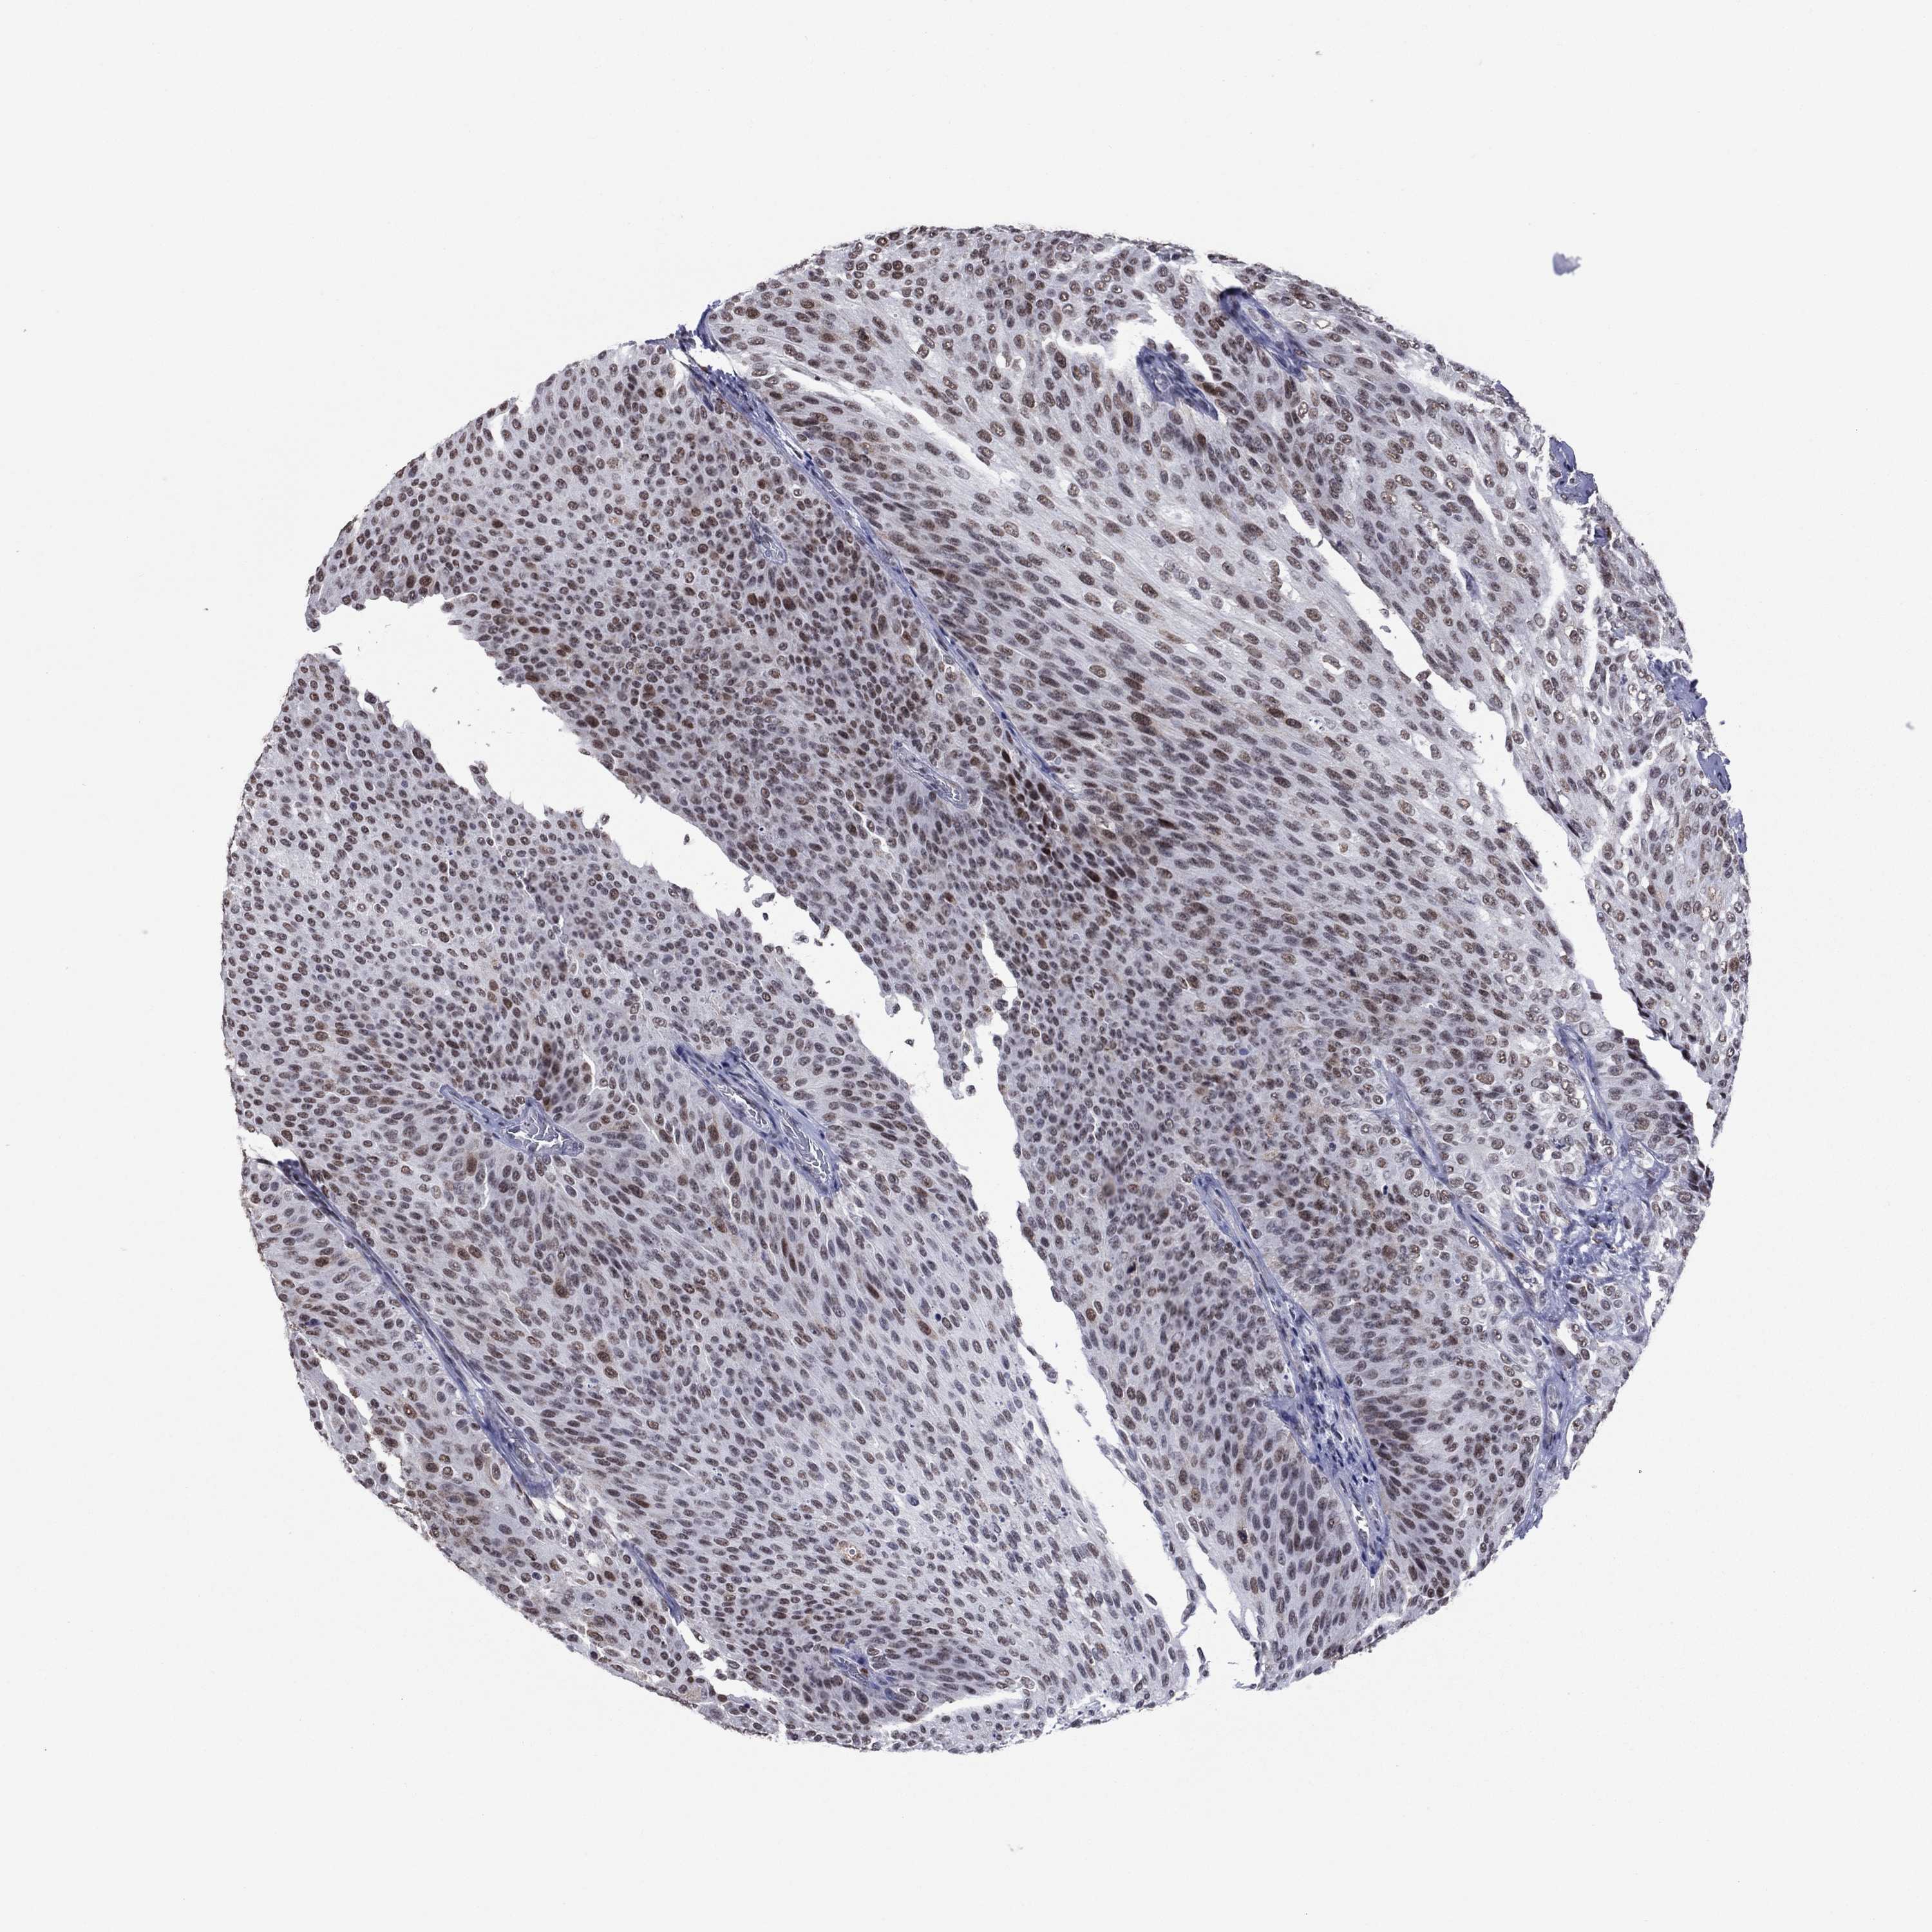

UROTHELIAL CANCER - Protein expressioni

A mouse-over function shows sample information and annotation data. Click on an image to view it in a full screen mode. Samples can be filtered based on level of antibody staining by selecting one or several of the following categories: high, medium, low and not detected. The assay and annotation is described here.

Antibody stainingi

Antibody staining in the annotated cell types in the current human tissue is reported as not detected, low, medium, or high, based on conventional immunohistochemistry profiling in selected tissues. This score is based on the combination of the staining intensity and fraction of stained cells.

Each image is clickable and will lead to virtual microscopy that enables deeper exploration of all samples and also displays staining intensity scores, fraction scores and subcellular localization as well as patient and tissue information for each sample.

Antibody HPA074922

Antibody CAB002784

Staining

High

Medium

Low

Not detected

Intensity

Strong

Moderate

Weak

Negative

Quantity

>75%

75%-25%

<25%

None

Location

Nuclear

Cytoplasmic/membranous

Cytoplasmic/membranous,nuclear

Urothelial carcinoma, High grade

Urothelial carcinoma, NOS

Urothelial carcinoma, Low grade

Adenocarcinoma, NOS